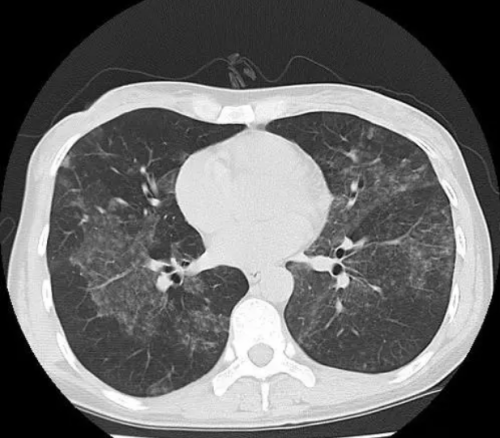

据袁江家人描述,3月2日,袁江像往常一样工作,但感觉浑身无力也没有胃口,以为得了个小感冒,就没有太在意。两天后,袁江的不适加重,在家休息了两天并没有缓解。3月12日,袁江开始发烧,体温上升至38℃左右,稍微活动一下就呼吸急促。3月14日他前往当地医院就诊,胸部CT显示双肺弥漫性病变,考虑感染性病变,需要住院诊治。

住院后,在短短2天时间内,袁江的病情以惊人的速度恶化了:反复高烧,体温屡屡超过39℃,伴随剧烈咳嗽,呼吸困难进行性加重,胸部CT复查显示双肺病灶明显增多,呈现“白肺”样改变。由于病情危重,3月17日,袁江由当地医院转入91短视频

此外,结核病患者感染的结核菌并不都是一样的情况,例如有种结核菌对我们最常使用的抗结核药物异烟肼和利福平均无效,产生耐药,感染了这种结核菌就是我们常常讲的耐多药结核病。袁江不仅因为体内的结核杆菌几乎侵犯了双侧所有的肺组织导致了呼吸衰竭、急性呼吸窘迫综合征,同时他体内的结核杆菌还侵犯了肺、肠道、泌尿系统和脑多个器官和部位。此外,他的耐药基因检测还显示他体内的结核菌同时对异烟肼、利福平和链霉素三种抗结核药物耐药,病情更为危重,治疗更为棘手,从而住进了重症监护室。